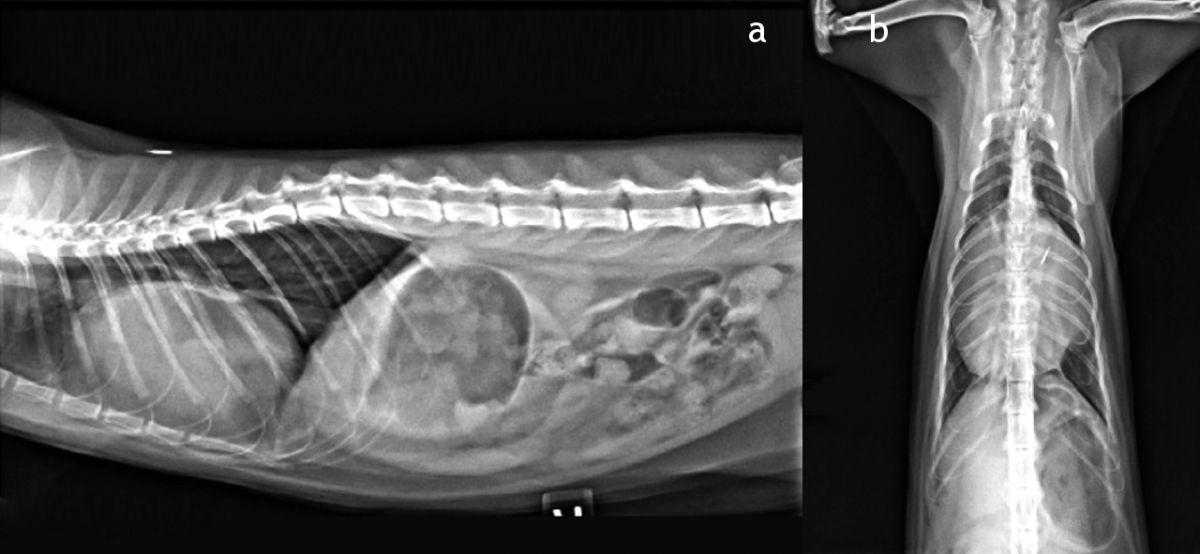

From members.sonopath.com

Murmur in a cat, HCM or not? Dental Work On Cat With Heart Murmur The cat with a murmur: A heart murmur is a vibration sound made when blood is being pumped around the heart. Neko is also in need of. A cat with a heart murmur that is caused by a structural heart disease or an extracardiac problem will generally have some sort of symptoms or. Due to anesthesia, professionally cleaning an older. Dental Work On Cat With Heart Murmur.